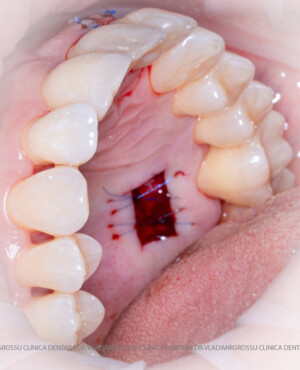

După extracția dentară, în intervalul de 6-12 luni, osul alveolar suferă un proces natural de remodelare, ceea ce conduce la scăderea volumului osos prin rezorbție. De aceea, inserția implantului dentar este ideală imediat după extracție sau, cel târziu, în primele 3-4 luni după aceasta.Scopul procedurilor de adiție osoasă este refacerea fundației osoase necesare pentru stabilizarea corectă a implantului dentar. Pentru ca un implant să reziste în timp la forțele masticatorii, este nevoie de o bază osoasă solidă și sănătoasă.

Procesul de refacere osoasă este complex, însă, simplificat, se bazează pe faptul că osul adăugat se integrează treptat, fiind înlocuit parțial cu os natural, oferind astfel suportul necesar implantului.